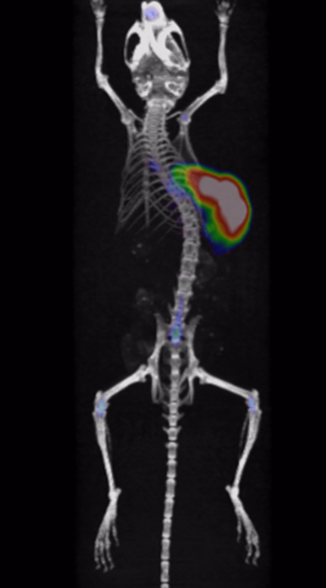

Through quality and process explorations with Zr-89-marked antibody conjugates, highly emissive-pure radiodiagnostic drug molecules are obtained and supplied for preclinical animal imaging and biodistribution studies, as well as subsequent IIT imaging in the clinic.

Rapid validation of Zr-89-marked antibodies

Fast lesion cumulation, most efficient distribution and high targeting ability for xenotransplanted tumor models.